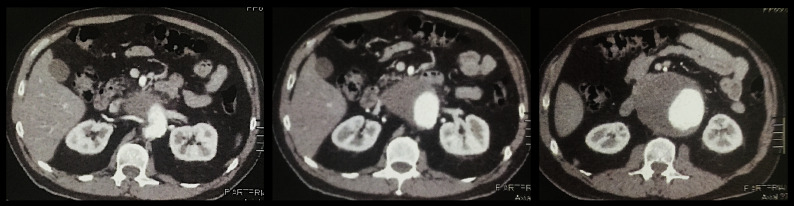

腹主动脉瘤在多种解剖情况下都会对治疗构成挑战,从而使血管内治疗变得更加复杂。肾下段腹主动脉瘤(JR-AAA)的定义是没有近端着床区,因此必须使用各种技术来获得足够的颈部以固定内支架,同时不引起肾动脉和内脏分支的闭塞。平行移植物技术、医生改良支架移植物、工业定制的内膜假体和现成的分支内膜假体是用于近端颈部不足的腹部动脉瘤的技术,但每种技术都有其适应症、局限性和风险。在这一治疗难题中,我们介绍了一例使用平行移植物技术对 JR-AAA 进行紧急血管内治疗的病例,取得了良好的中期效果,并讨论了治疗方案。

Abdominal aortic aneurysms can constitute a therapeutic challenge in several anatomical scenarios, making endovascular treatment more complex. A juxtarenal abdominal aortic aneurysm (JR-AAA) is defined by the absence of a proximal landing zone in the infrarenal segment and, therefore, techniques must be used to obtain an adequate neck for fixing the endoprostheses without provoking occlusion of renal arteries and visceral branches. The parallel grafts technique, physician-modified stent-graft, industry customized endoprostheses, and off-the-shelf branched endoprosthesis are techniques used in abdominal aneurysms with inadequate proximal neck, but each technique has its indications, limitations, and risks. In this therapeutic challenge, we present a case of urgent endovascular treatment of a JR-AAA using a parallel grafts technique, with good medium-term results, and discuss the therapeutic options.